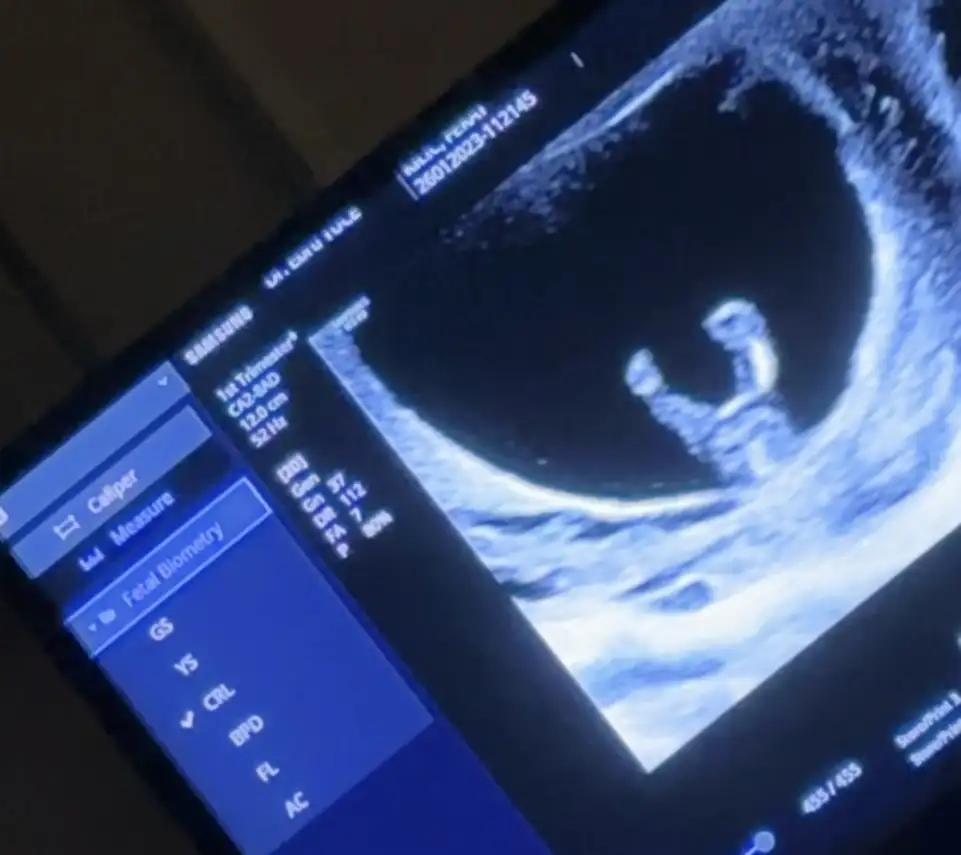

Belli oldumu cinsiyetiniz? Arkası dönük sanırım burdaBana da tahminde bulunun nolur 11+3![]()

Cinsiyeti kesin olarak ne acabaCanlar arkadaşımın 11+3 günlük gebeliğinde doktoru direk cinsiyeti bilmiş, kız demiş ultrason görüntüleri gerçekten de çok net bacak arası çekilmiş ve boş. Ama benim de başıma aynı durum gelmişti kesin kız denildi bacak arası böyle bomboştu hatta 16. Haftamda erkek çıktı bu durum da bizim kafamızı karıştırdı iyice. Cinsiyet tahmini yapan arkadaşlar yardımcı olabilirler mi?![]()

bana da kız dendi ve sürpriz oğlum oldu. doktor o kadar da emindi.Canlar arkadaşımın 11+3 günlük gebeliğinde doktoru direk cinsiyeti bilmiş, kız demiş ultrason görüntüleri gerçekten de çok net bacak arası çekilmiş ve boş. Ama benim de başıma aynı durum gelmişti kesin kız denildi bacak arası böyle bomboştu hatta 16. Haftamda erkek çıktı bu durum da bizim kafamızı karıştırdı iyice. Cinsiyet tahmini yapan arkadaşlar yardımcı olabilirler mi?![]()